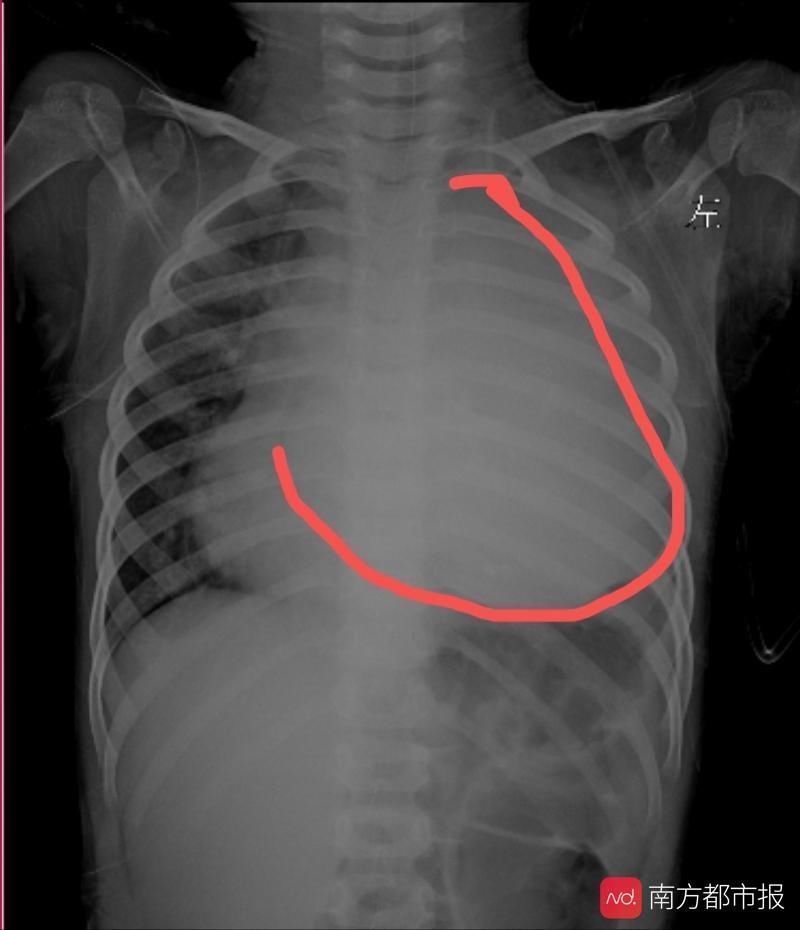

手术前,小星星的左侧胸腔已经被完全挤占

文章插图

手术后,原本被挤占的肺、心开始回归正常位置